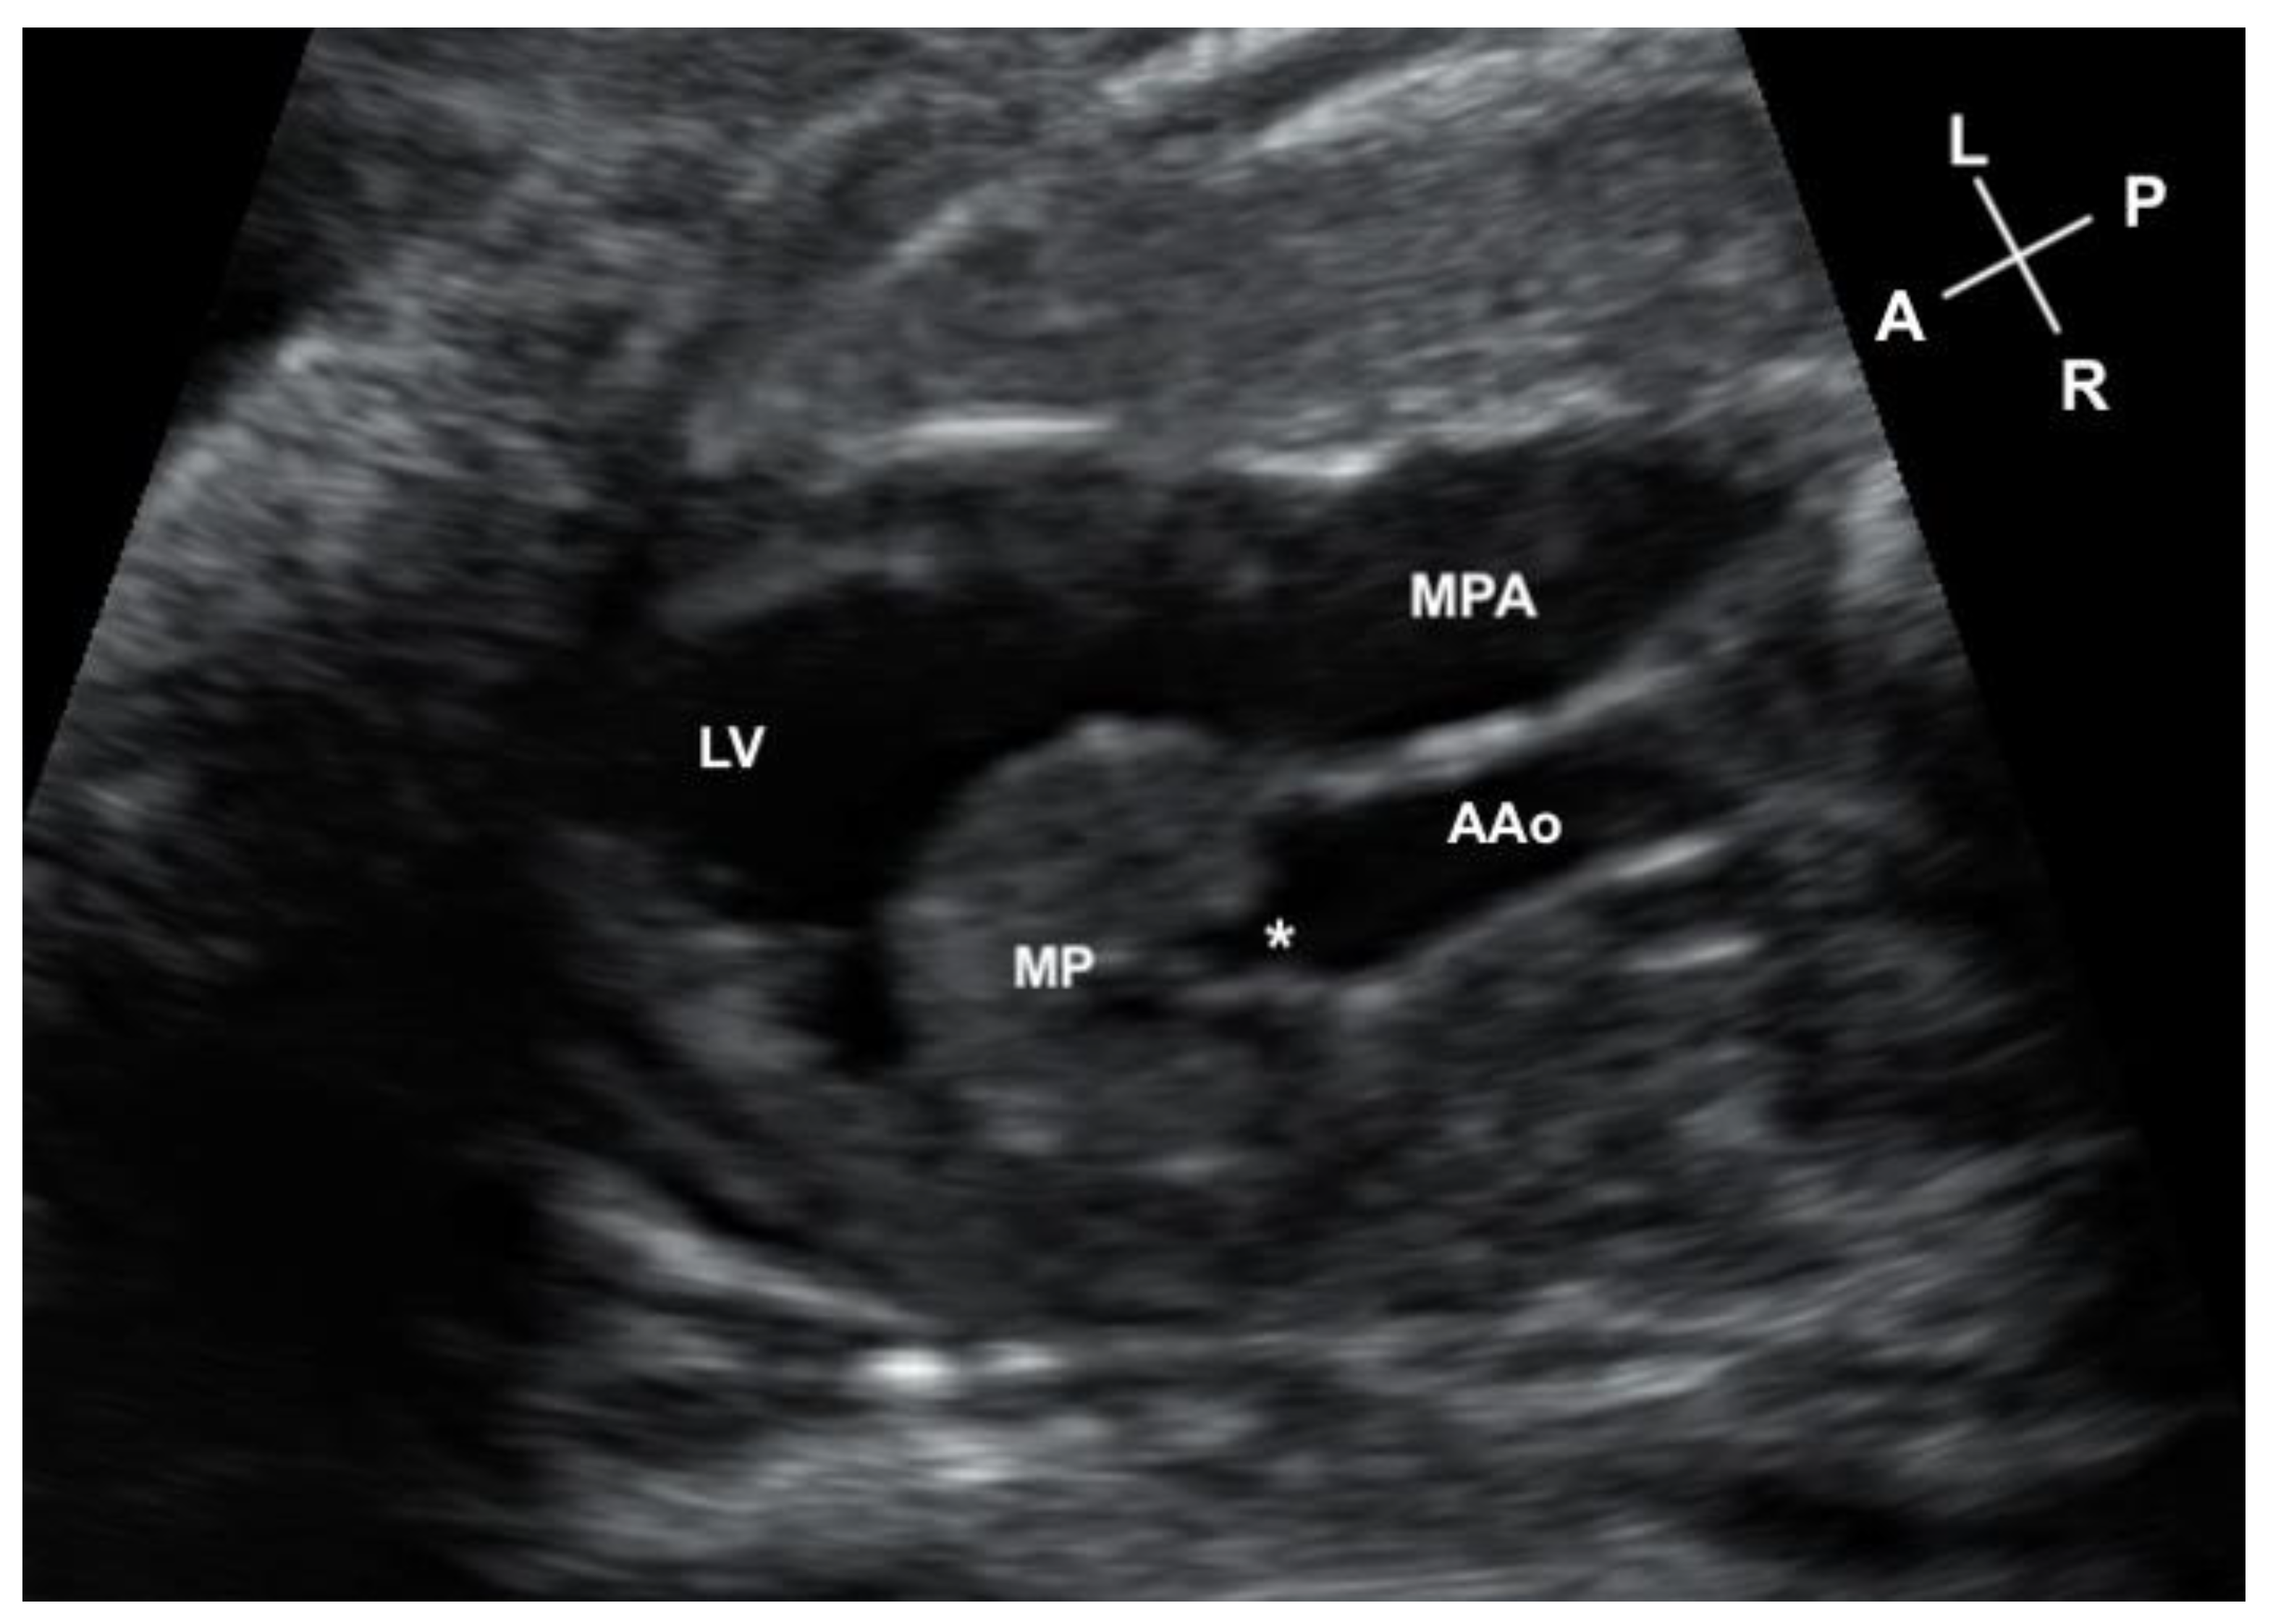

2. Case Description